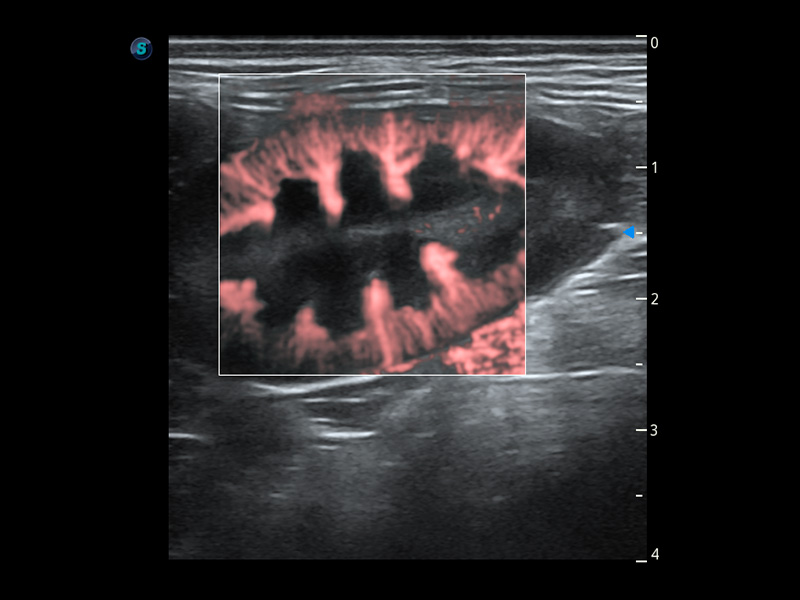

ProPet 60 作为一款高端台式动物超声设备,为动物医生的日常诊断提供了一系列贴合动物临床需求、解决临床实际问题的高级成像功能。凭借全系列高清探头,满足医生对腹部、心脏、生殖、浅表、肌骨等成像的所有需求,切实帮助您提升检查效率,提高诊断信心。

动物是人类最亲密的朋友和最值得信赖的伙伴。玖鼎集团也一直致力于探索动物专用的超声影像解决方案。 全新推出的ProPet系列,是玖鼎集团在动物超声影像智能化、专业化、精准化的一次跨越式革新。动物不能用言语来表述自己的不适,通过超声影像,ProPet系列搭建了动物医生与不同物种沟通的“桥梁”,为动物医生注入了“治愈之力”。